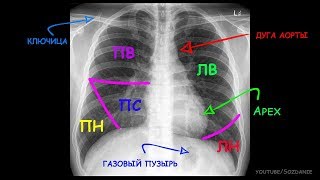

Как выглядит воспаление легких на снимке?

Тем не менее, на вопрос, покажет ли флюорография пневмонию, ответ — да, чаще всего — да. Но в основном речь идет о выявлении самого факта заболевания, специфичность в этом типе исследования маловероятна, особенно когда болезнь находится в начальной стадии. Если снимок сделан на поздней стадии патологического процесса, можно различить очаговую и крупную пневмонию. На рисунке ниже показано, как выглядят эти типы пневмонии.

Опытный специалист, глядя на картинку, обращает внимание на следующие нюансы:

- Тонкие линейные ткани в большинстве случаев нечеткие, но это все же один из симптомов развития пневмонии.

- Наличие одной или нескольких световых точек, так называемых очаговые тени в проекции органа.

- Нерегулярное затемнение и яркость.

- Увеличение или утолщение легочных корней.

- Усиление легочного рисунка, образованного сосудами и указывающего на воспалительный процесс.

- Аномальное положение мышцы диафрагмы.

- Патологические отклонения в расположении органов средостения, их смещение, могут говорить о скоплении жидкости или воздушных масс в плевральных полостях.

Яркий пример — проникновение, выглядывающее сквозь тень сердца. В этом случае для уточнения диагноза необходимо сделать два проекционных рентгеновских снимка.